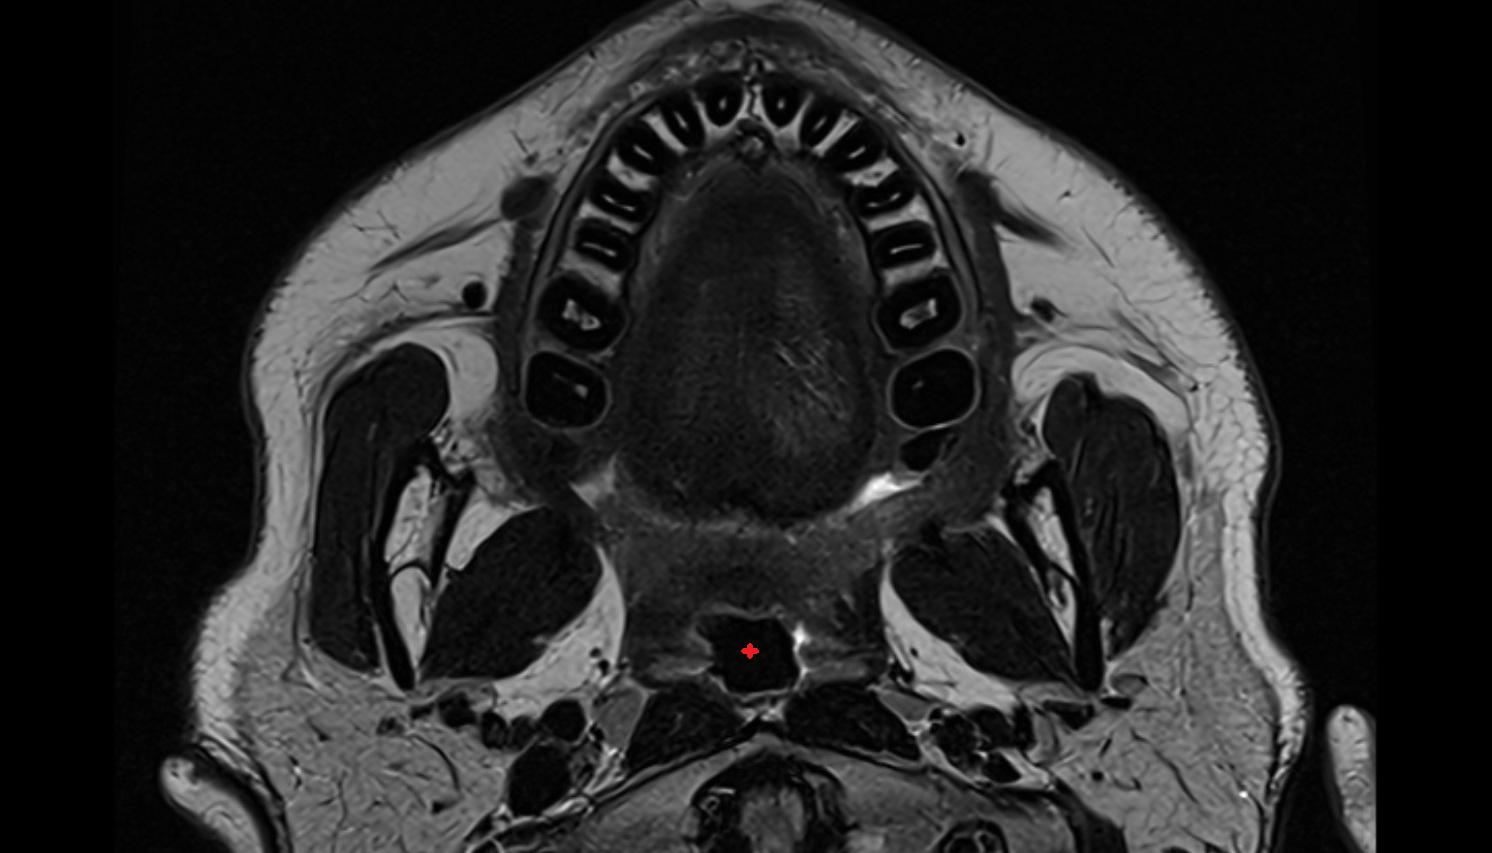

- Temporomandibular joint

- Mandibular condyle

- Mandibular fossa

- Lateral pterygoid muscle

- Masseter muscle

- Medial pterygoid muscle

- Temporalis muscle